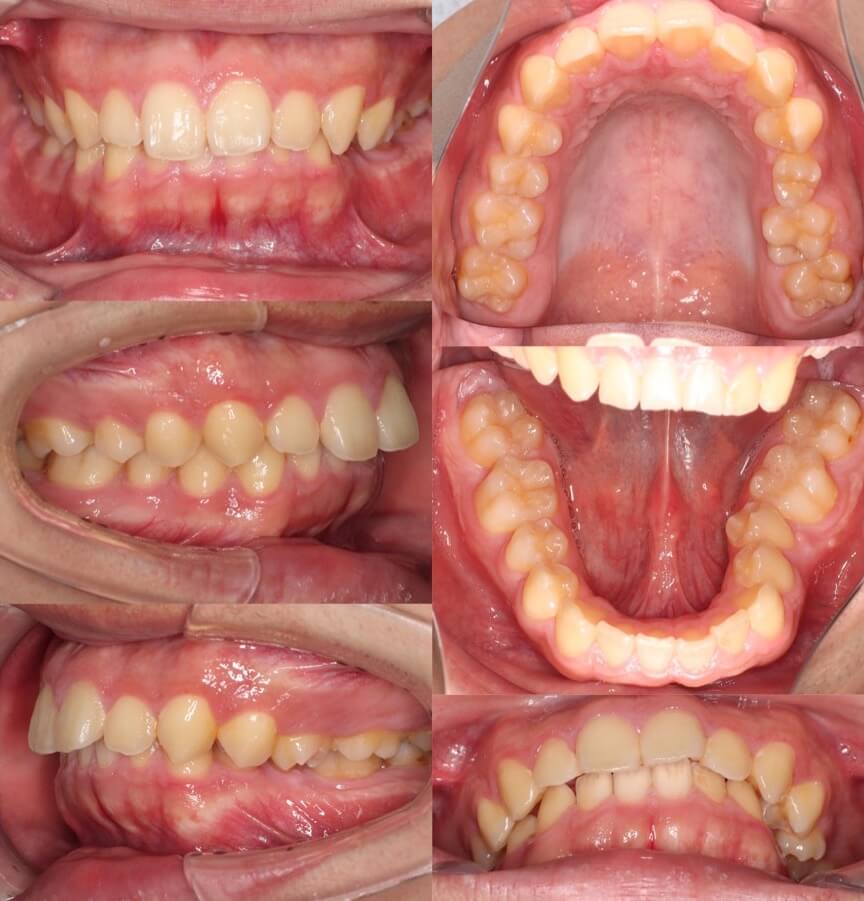

高校生女子・マウスピース型矯正

<顔のビフォーアフター>

<症例概要>

主訴:上の前歯の歯並び

年齢・性別:15歳女子(高校生)

住まい:千葉県佐倉市

症状:過蓋咬合・叢生

治療方針:上下顎前歯前方傾斜・ストリッピング

治療装置:マウスピース型矯正装置(アライナー装置)

治療期間:11か月

アライナー枚数:17+11ステージ

リテーナー:上プレートタイプ・下フィックスタイプ

治療費用:990,000(税込)

代表的副作用:痛み・治療後の後戻り・歯根吸収・歯髄壊死・歯肉退縮

▶︎その他の副作用

※マウスピース型カスタムメイド矯正歯科装置は完成物薬機法対象外の矯正装置であり、医薬品副作用被害救済制度の対象とはならない可能性があります。

過蓋咬合のケースです。マウスピース型矯正装置を使用し、非抜歯にて治療を行いました。途中から顎間ゴムも使用して、噛み合わせの仕上がりも問題ありません。マウスピース矯正はケースによっては従来型の矯正治療より早く終える事ができる事もあります。「早く」「痛くなく」なら「目立たない」という理由以外にマウスピース装置を選択するメリットはありますよね。